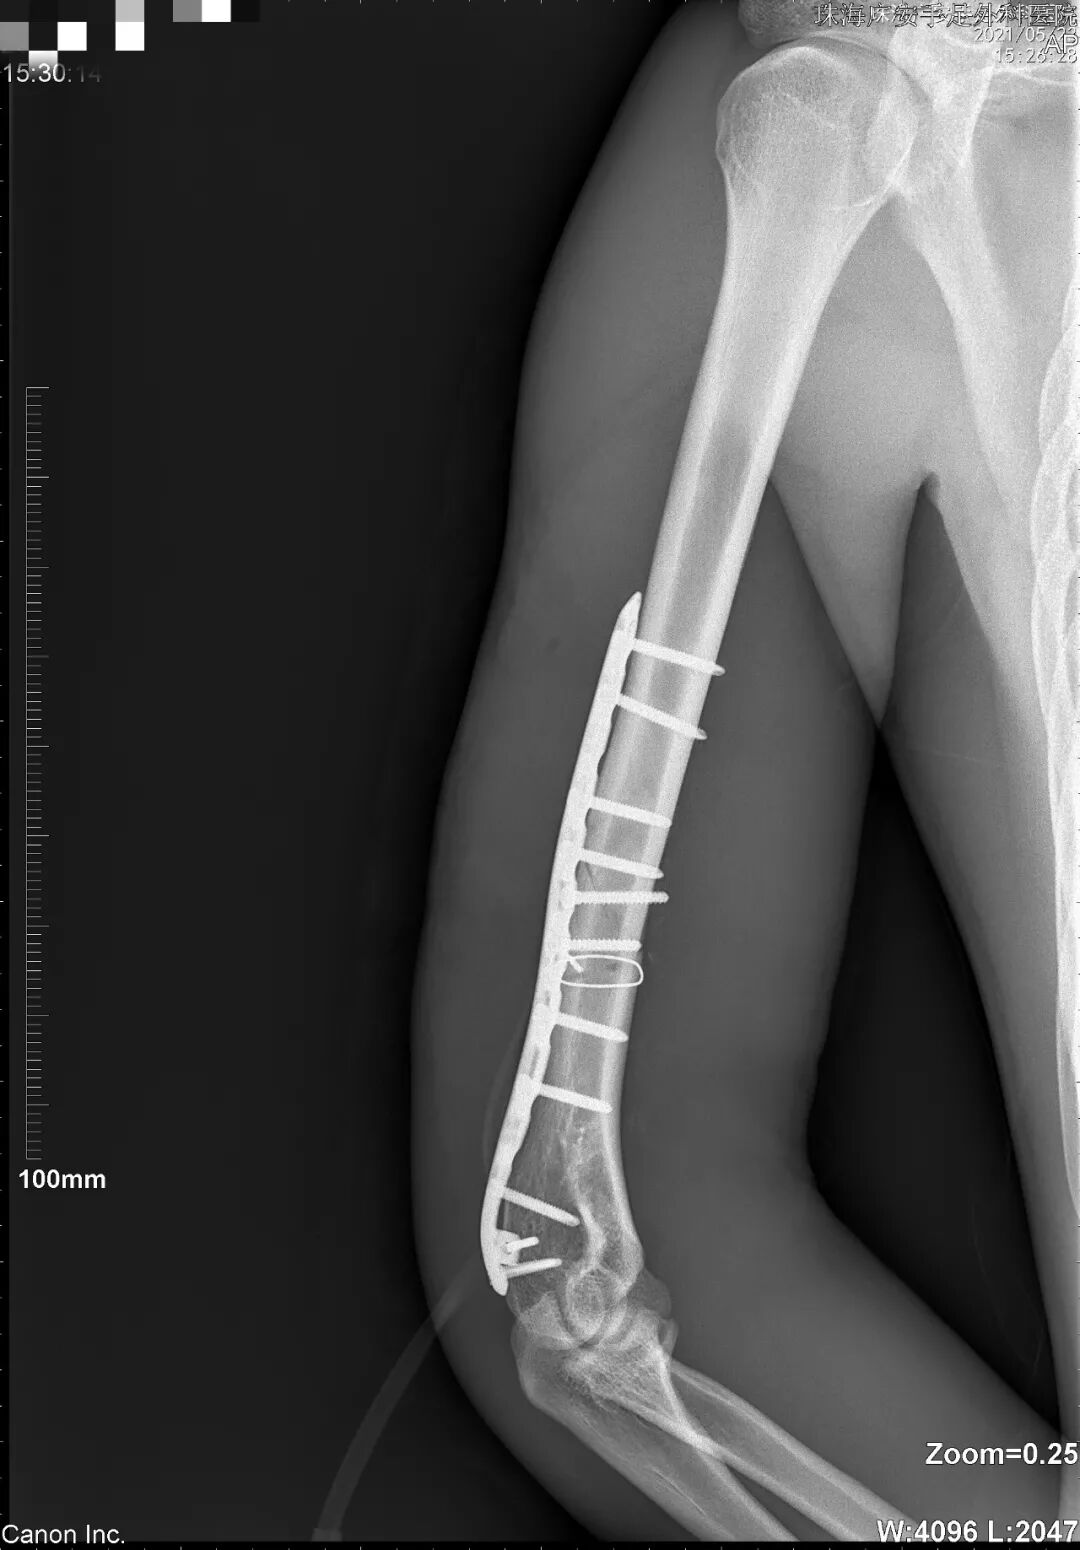

后来到我院就诊时,姜先生右上臂肿胀、压痛明显,急诊X线显示其右肱骨骨折,住院接受右肱骨骨折切开复位内固定术。